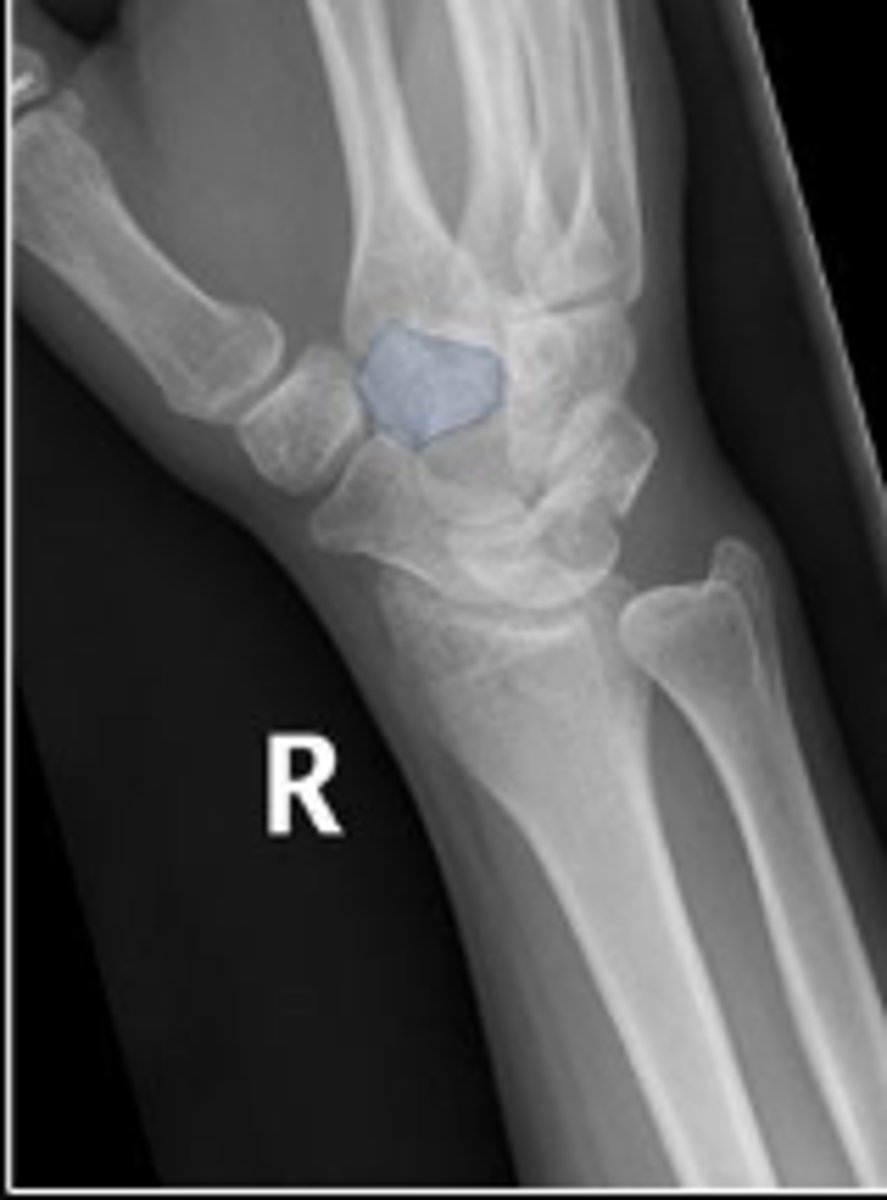

Medial oblique of the right wrist

What is the name of the radiographic view?

Right scaphoid

What is outlined?

What is the arrow pointing to?

Right trapezium